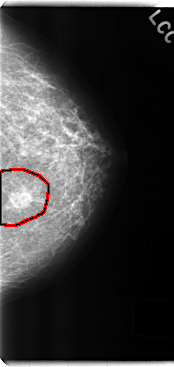

C_0215_1.LEFT_CC

LEFT_CC LINES 4768 PIXELS_PER_LINE 2256 BITS_PER_PIXEL 12 RESOLUTION 50 OVERLAY

FILE: C_0215_1.LEFT_CC.OVERLAY

TOTAL_ABNORMALITIES 1

ABNORMALITY 1

LESION_TYPE MASS SHAPE OVAL MARGINS SPICULATED

ASSESSMENT 5

SUBTLETY 5

PATHOLOGY MALIGNANT

TOTAL_OUTLINES 1

BOUNDARY